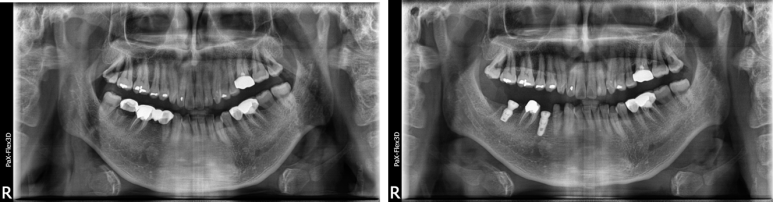

만약 임플란트 식립해야 할 치아가 왼쪽, 오른쪽 위 아래 가리지 않고 다양한 위치에 있을 경우에는

왼쪽을 먼저 치료를 완료하고 그 이후에 오른쪽 치료를 진행할 수 있으므로 임플란트기간이 더 오래걸리게 되는 것입니다.